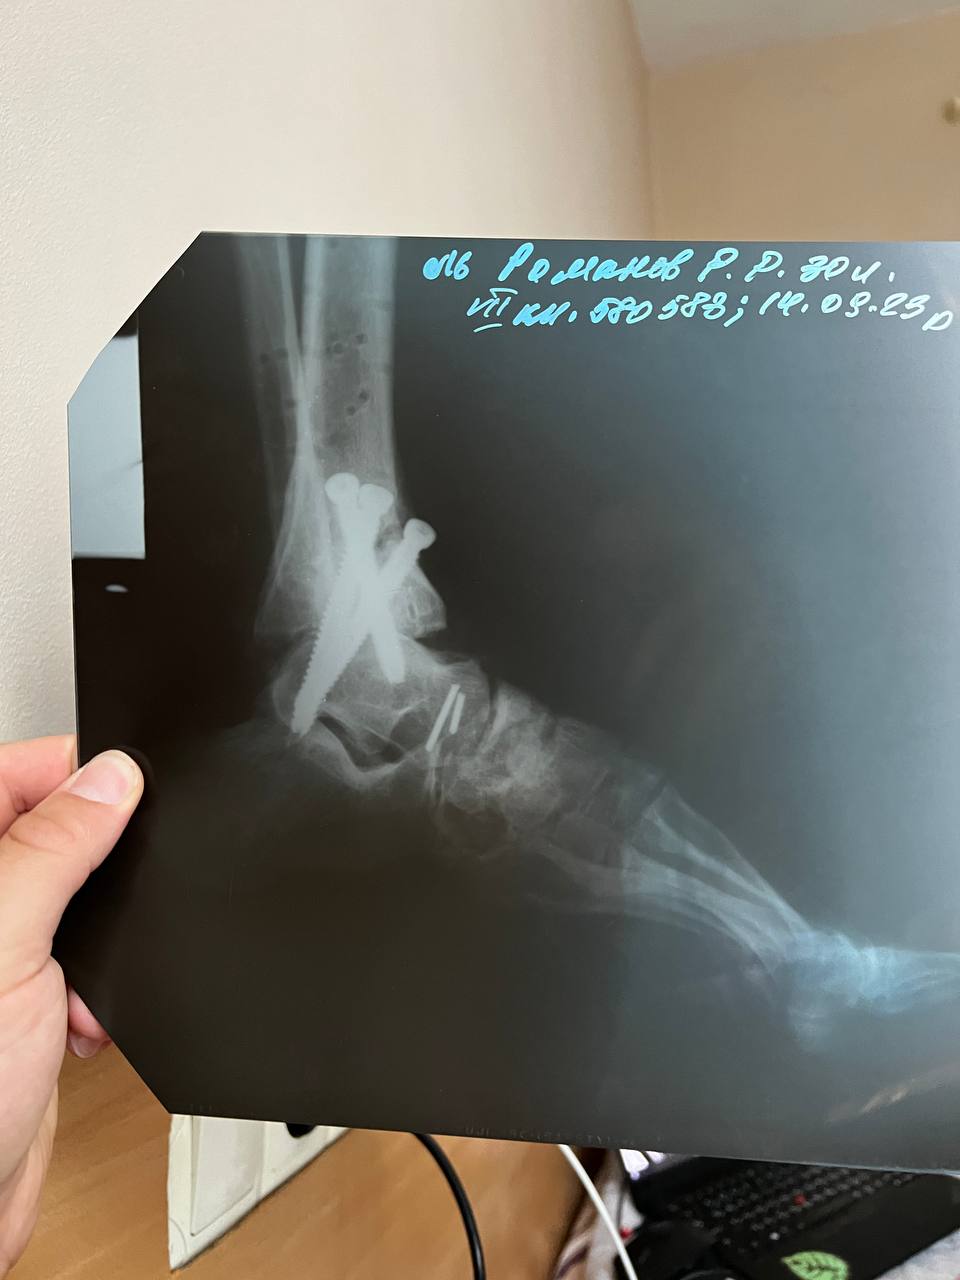

У Руслана був закритий перелом лівої ноги - кінцівка була зламана нижче коліна до кінчиків пальців. Йому за більш ніж рік провели чотири операції, і зараз замість суглоба три великих гвинти. Також після травми довелося з обох сторін зашивати щелепу.

"Відновлення триває й зараз, вже більше року. Через півроку після поранення почав ставати на ноги. Три місяці я взагалі майже не ставав - організм був практично на нулі, крутилося в голові, не міг спати. Плюс - цілий рік у мене були дуже сильні болі, бо зросталися кістки. Було дуже важко психологічно і фізично. Особливо перші три місяці були дуже важкі. Зрештою почав ходити на двох милицях, потім з однією милицею. Намагався ходити без милиці, але не виходило. І зараз можу пройти лише невелику відстань сам", - ділиться чоловік.